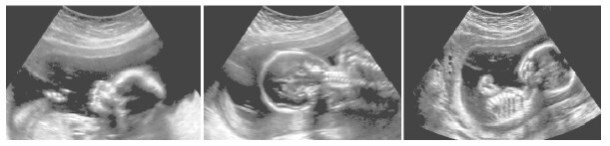

Иллюстрация к книге — Взламывая анатомию [image243.jpg]

Ультразвуковое сканирование растущего плода позволяет врачам следить за развитием ребенка.